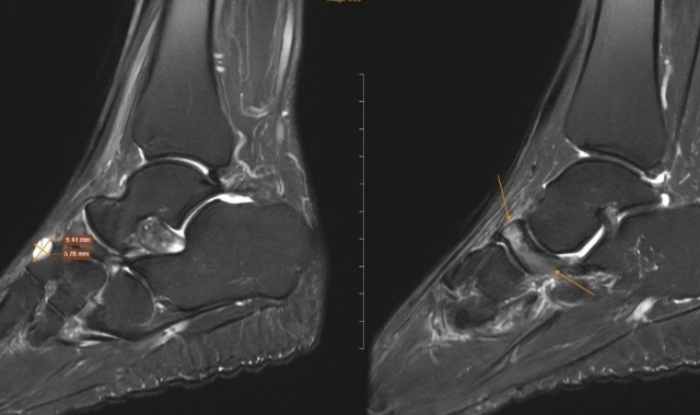

Tại cơ sở y tế, bác sĩ chỉ định chụp cộng hưởng từ để đánh giá tổn thương sâu. Kết quả, xương ghe bàn chân phải bị xẹp và biến dạng điển hình, kèm đặc xương dưới sụn và phù tủy rõ rệt. Ngoài ra, hình ảnh còn ghi nhận tổn thương thoái hóa khớp cổ chân trái, phù tủy xương sên, viêm dây chằng và dịch khớp cổ chân.

Hình ảnh chụp MRI cho thấy những dấu hiệu đặc trưng của Hội chứng Mueller-Weiss ở chân phải.

Bác sĩ chẩn đoán hình ảnh cho biết việc phát hiện bệnh phụ thuộc nhiều vào các phương tiện cận lâm sàng. X-quang có thể cho thấy xương ghe biến dạng dạng dấu phẩy hoặc xẹp nhỏ. Chụp CT giúp đánh giá rõ tình trạng xơ cứng và phân mảnh xương. Cộng hưởng từ được xem là phương pháp nhạy nhất, phát hiện sớm phù tủy xương trước khi hình thái xương thay đổi, đồng thời đánh giá mức độ hoại tử.